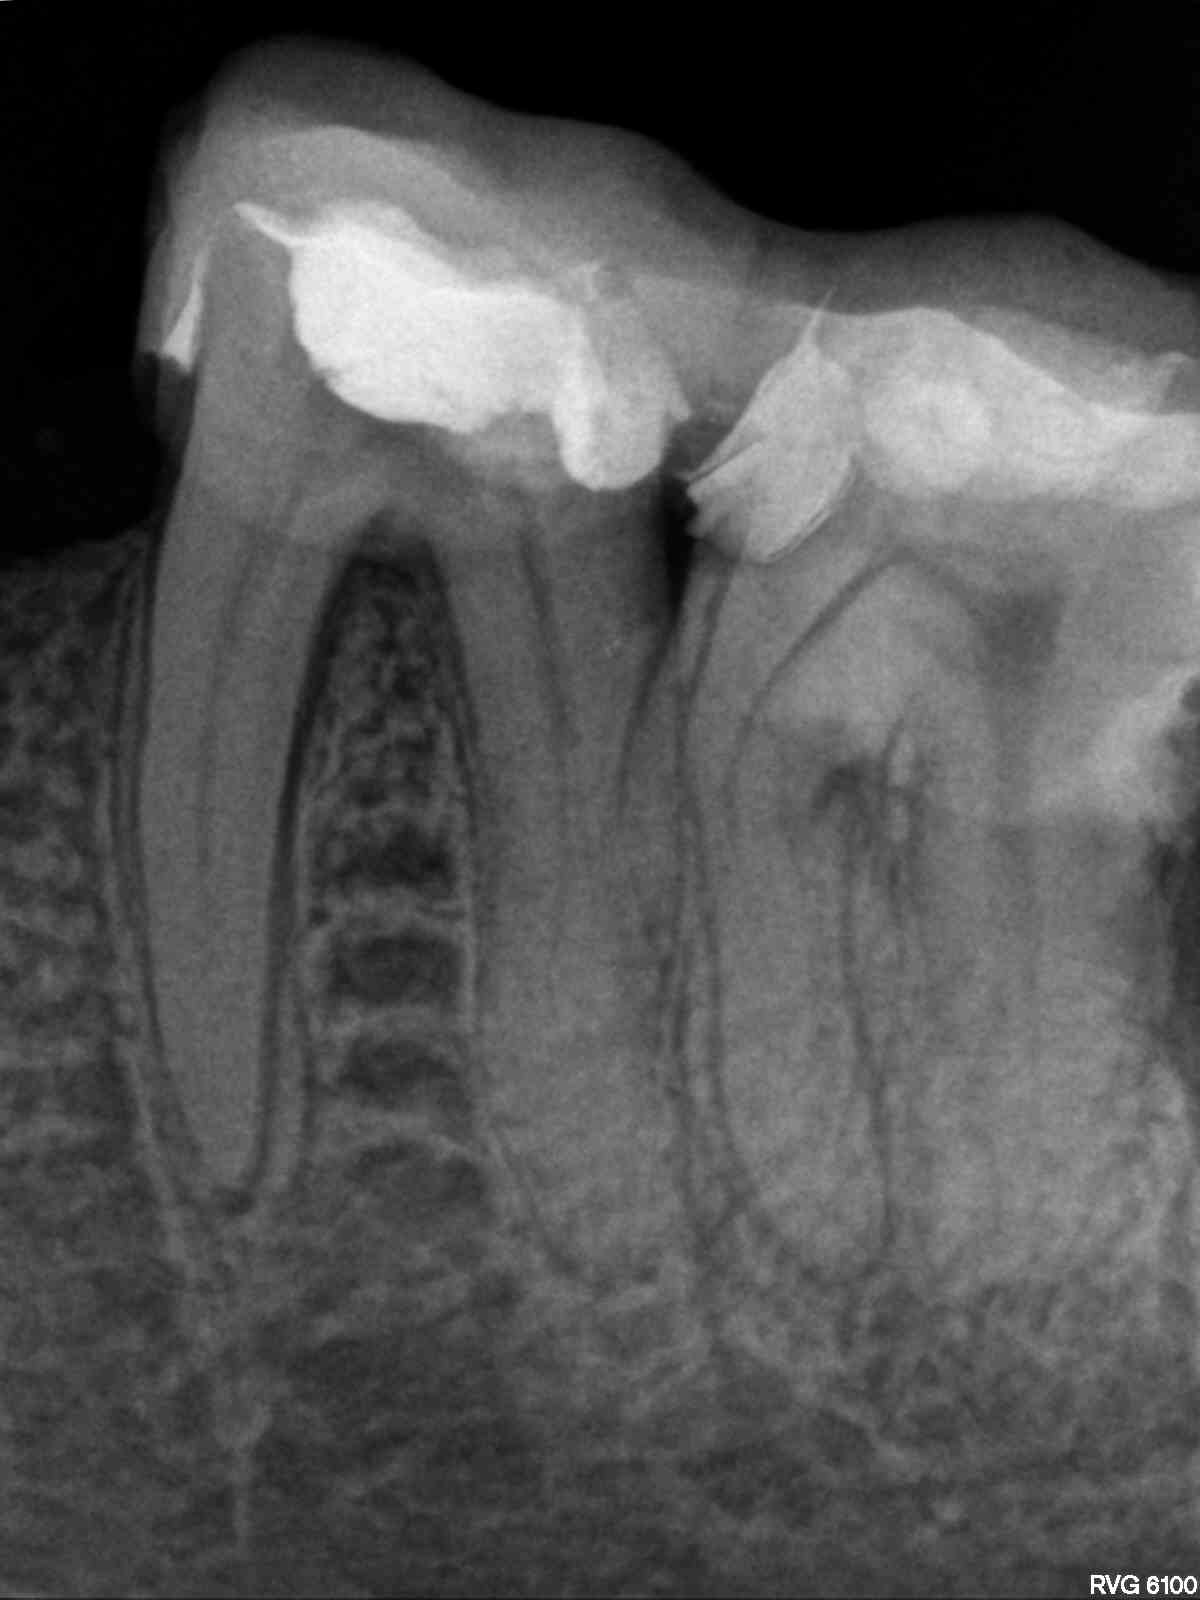

R1

1200 × 1600

Anatomie unterer Molaren (10)